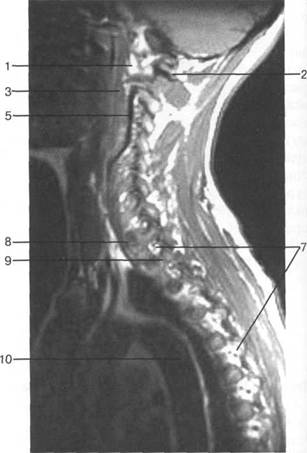

MPT. Cw_v.

V2; Th,; Thn;